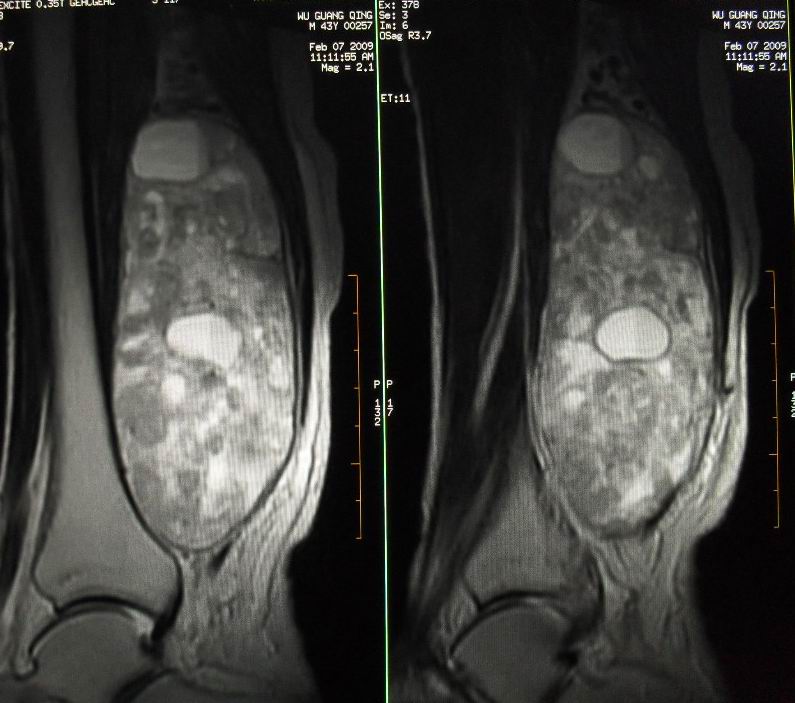

患者男43,右小腿后部软组织肿块2~3年,近期增大明显。平扫加强化。已手术。

1)呈等长t1混杂t2信号,其内见多发类圆形长t1长t2异常信号,病灶主要沿肌间隙生长,但有完整的包膜.gd_dtpa显示:病灶呈明显不均匀的强化,但未见迂曲的强化血管影.

呈等长t1混杂t2信号,其内见多发类圆形长t1长t2异常信号,病灶主要沿肌间隙生长,但有完整的包膜

本病例软组织肿块大,内信号不均匀,有多个囊变区,包膜完整,本片经山东省医学影像研究所mri室王主任会诊术前考虑良性肿瘤,不排除恶变,在北京某医院手术,穿刺及术后病理均为良性,未发现恶变。

本病例软组织肿块大,内信号不均匀,有多个囊变区,包膜完整,本片经山东省医学影像研究所mri室王主任会诊术前考虑良性肿瘤,不排除恶变,在北京某医院手术,穿刺及术后病理均为良性神经鞘瘤,未发现恶变。[face=宋体][/face]

谢谢楼主反馈手术结果!该病灶巨大,但与周围组织分界清晰,其内低密度规整,均支持良性病变。